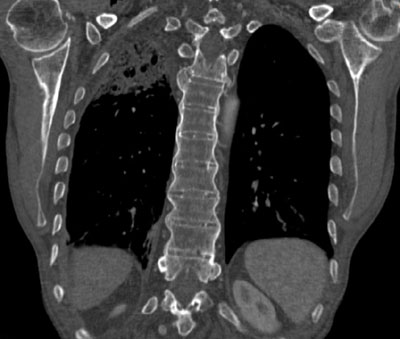

Vor allem in Seitenbild sind die Knochenspangen zwischen den Wirbelkörpern gut zu erkennen. Damit ist die Diagnose eines Morbus Bechterew praktisch klar. Noch eindrücklicher sieht man die Knochenspangen im CT (siehe unten).

Zusätzlich besteht aber noch ein anderer Befund ...

CT Thorax